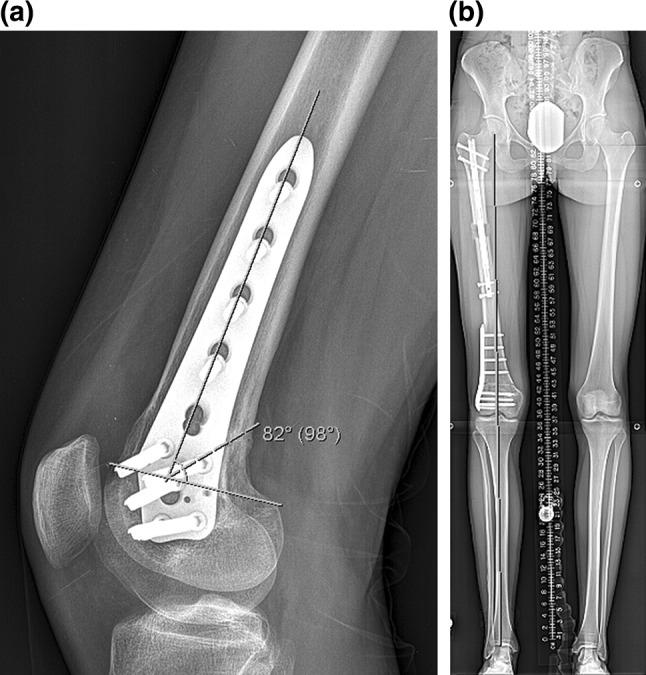

Salter Harris fractures of the distal femur can lead to growth disturbance with resulting leg length inequality and knee deformity. We have looked at a case series (3) of patients who presented with a distal femur flexion malunion and shortening treated with a distal femoral osteotomy and plating and a proximal femoral osteotomy with a magnetic internal lengthening nail. Does a two-level osteotomy and internal fixation approach provide a reliable result both radiographically and functionally? The average knee extension loss was 12°, LLD 47 mm, PDFA 65°, MAD 2 mm. The patients were treated with an acute, posterior, opening wedge osteotomy of the distal femur stabilized with a lateral plate and screws and grafted with cancellous chips and putty. A second osteotomy was made proximally in the femur percutaneously, and the internal lengthening nail was inserted. Lengthening was done at approximately 1 mm/day. The average extension gain was 12°; amount of lengthening at the proximal site was 40 mm, LLD was 3 mm. The average PDFA was 81°, and MAD 3 mm. There were no complications. Functional results were excellent. Bone healing index was 24 days/cm. The average distance from the distal osteotomy to the joint line was 57 mm. The technique of two-level femur osteotomy stabilized with a plate and lengthening nail yielded excellent results with acceptable correction of deformity, full knee extension, and improved function. There were no complications including implant failure, infection, need for blood transfusion, knee stiffness, nonunion, compartment syndrome, or malunion.

摘要